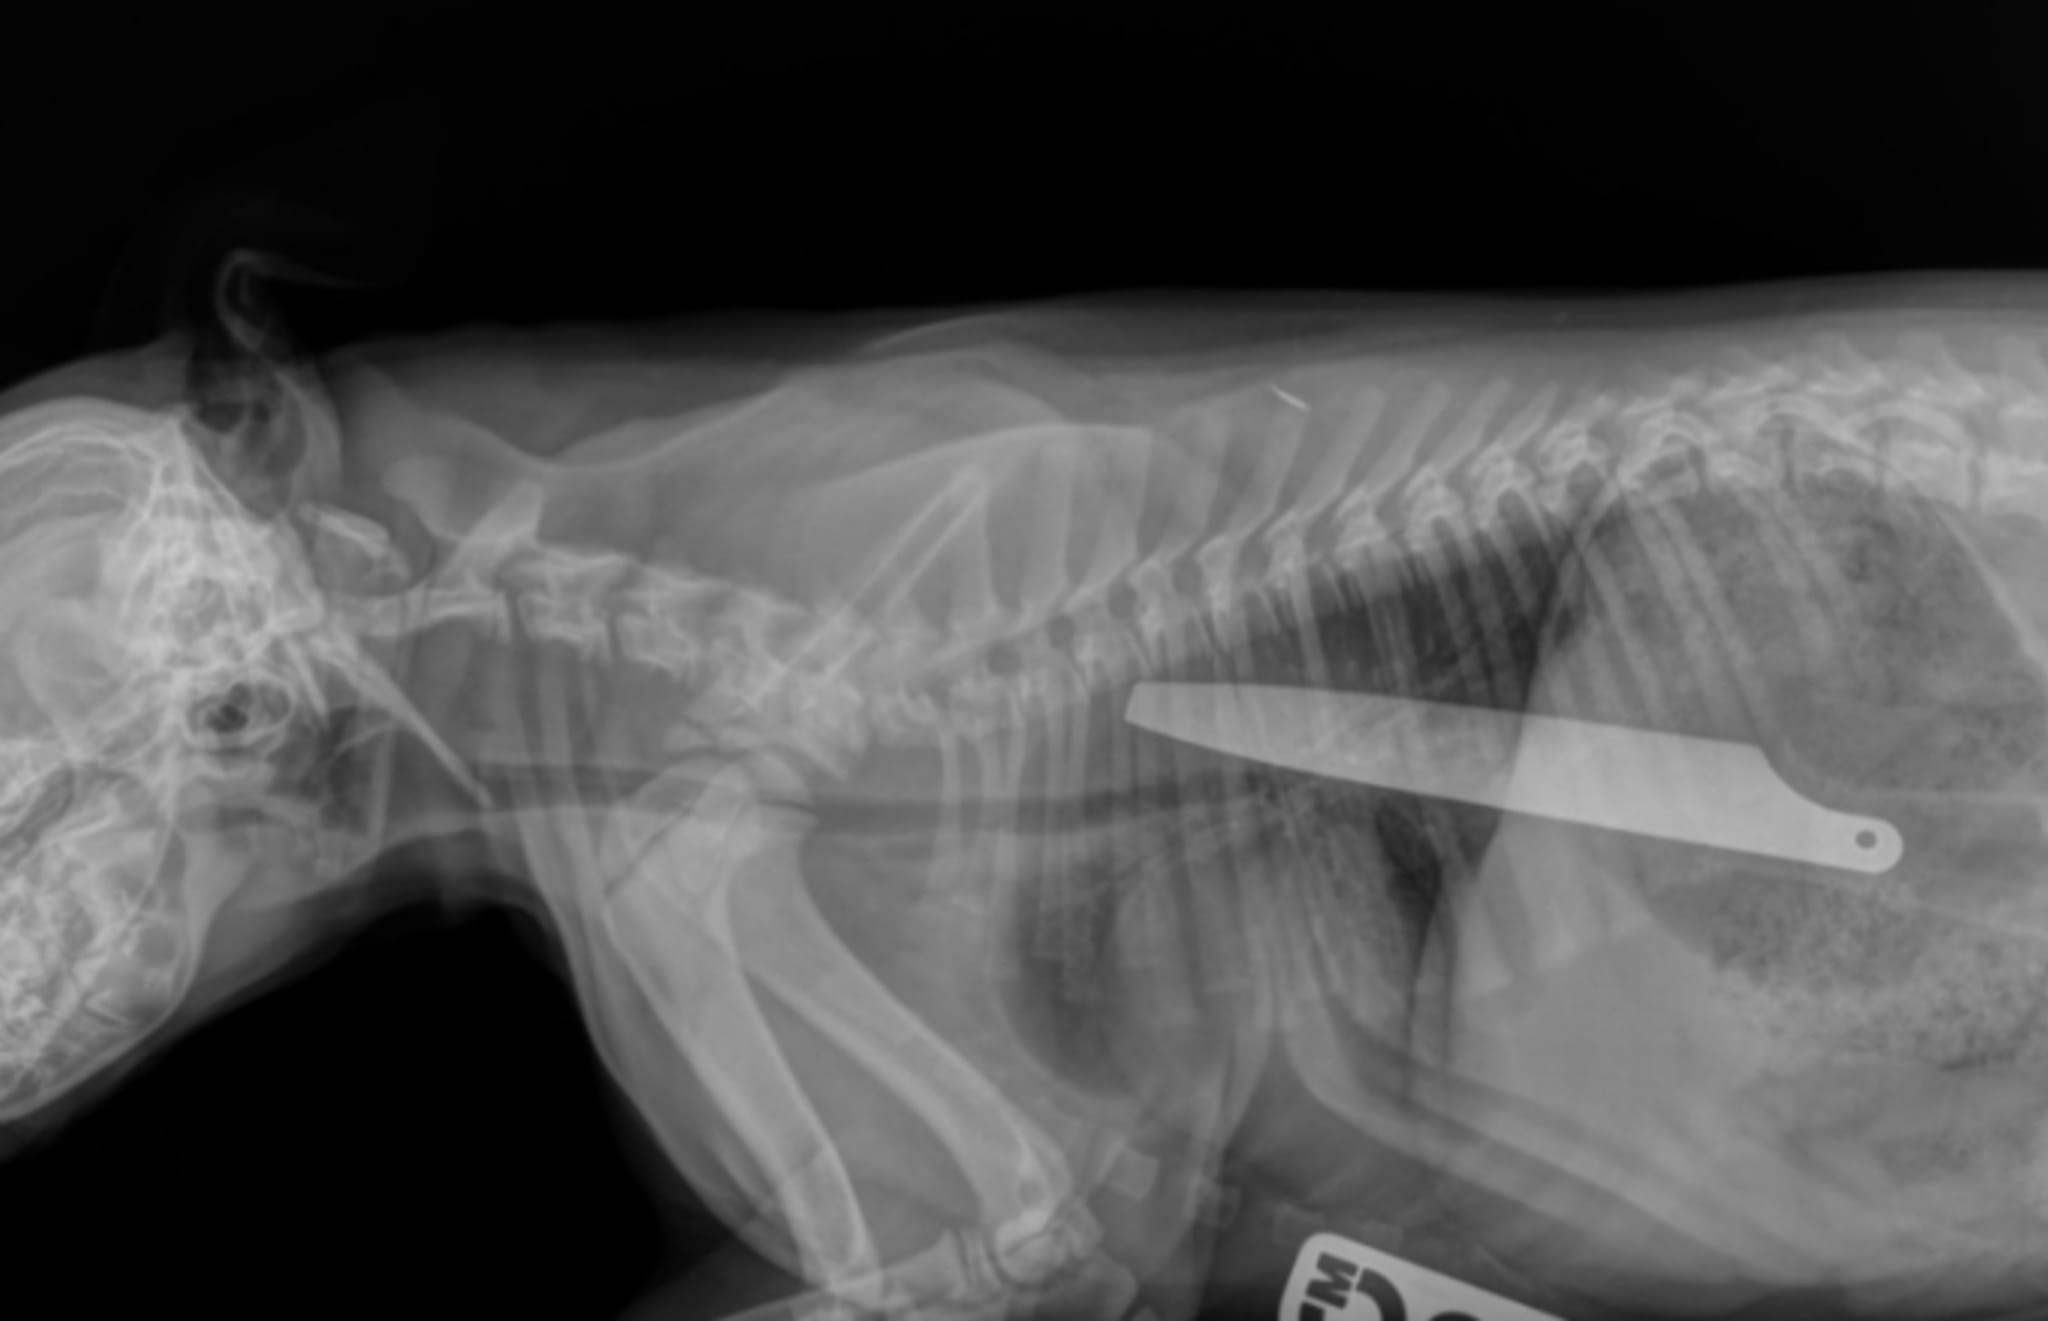

Macie entered surgery after having some x-rays taken—x-rays described by one veterinarian as unlike anything she's ever seen. "I've never seen an x-ray like Macie's," Emily Ronald said in a press release. "She was extremely lucky to survive. Her saving grace was that she swallowed the handle-end first. The blade-end would undoubtedly have pierced her organs, likely causing fatal injuries."